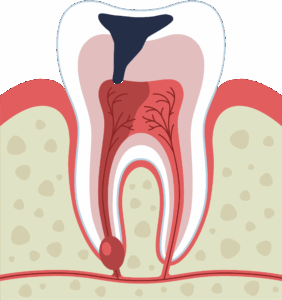

歯の内部には根管という歯髄(神経や血管)が入っている空間があります。外傷や虫歯によって歯髄に炎症を起こしたり、細菌感染を起こした場合に行われるのが根管治療です。根管内部の炎症を起こした歯髄や感染した部分の歯を除去し、洗浄消毒を行い、最終的には根管に詰め物を行って、また噛める状態にしていきます。

細菌感染した歯髄と歯の根の先に溜まった膿

神経に達するほど大きな虫歯(中央の黒い部分)が出来ています。